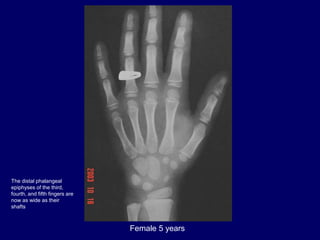

Female 5 years

The distal phalangeal

epiphyses of the third,

fourth, and fifth fingers are

now as wide as their

shafts